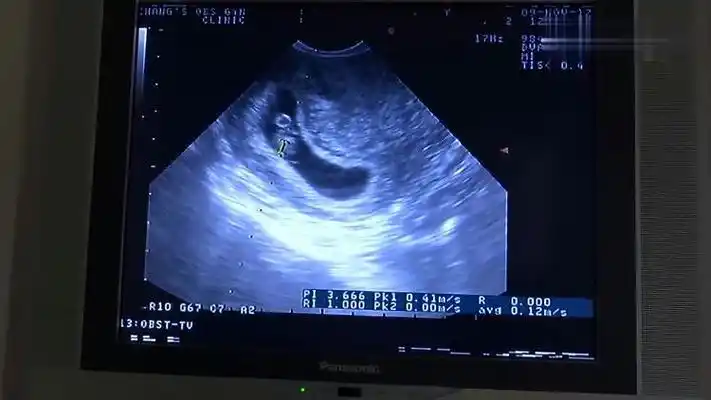

怀孕两个多月孩子没有胎心?答案原来如此!你知道了吗?_情况_检查_复查

明明怀孕了,可孕囊怎么是空的?67_胚胎_检查_因素